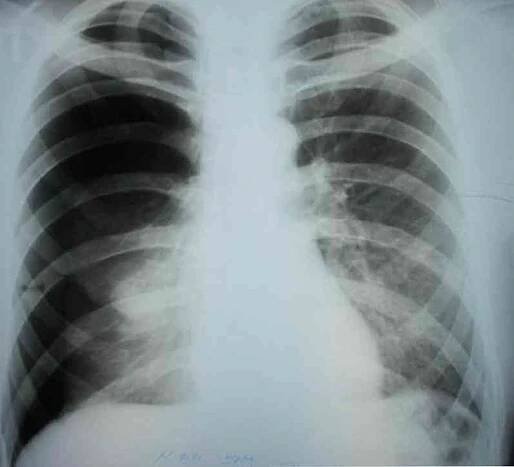

Rentgenový snímek – pneumotorax levé plíce a nahromadění vzduchu v pleurální dutině hrudníku (bílá barva). Zdroj: Getty Images